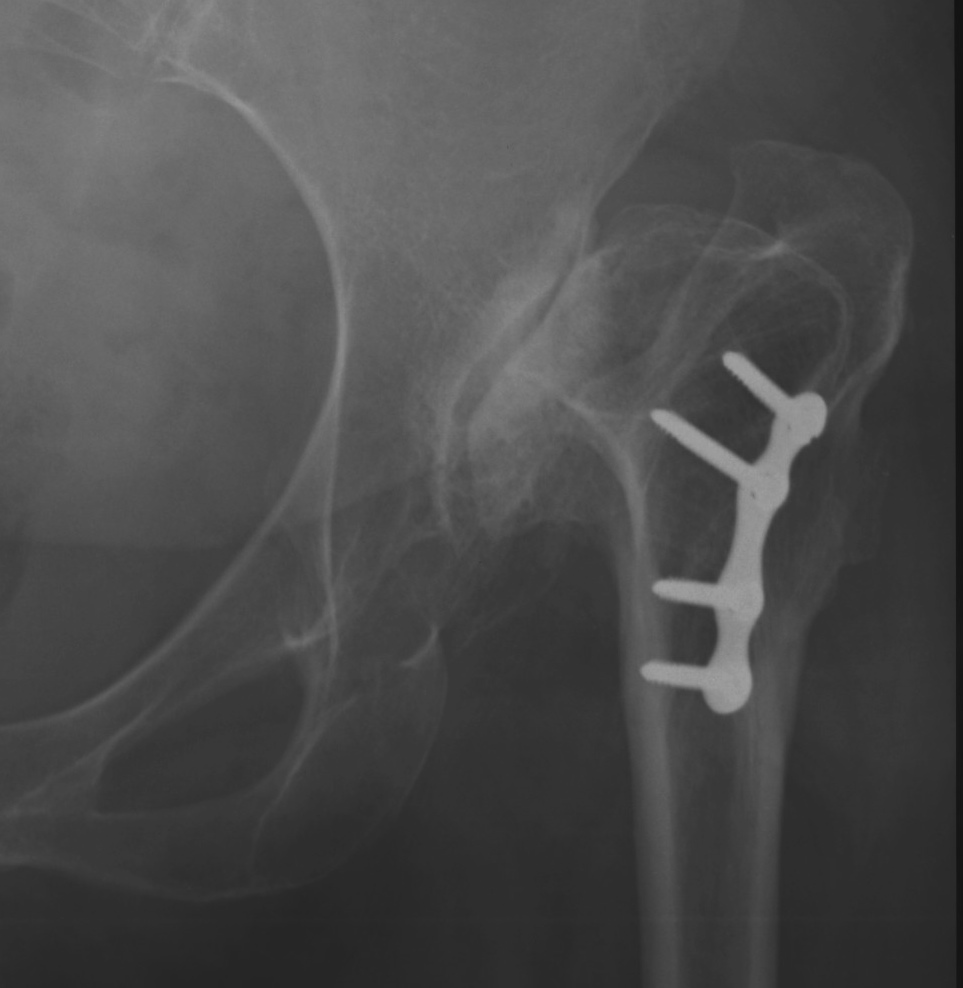

Crowe I

Crowe II

Crowe III

Crowe IV